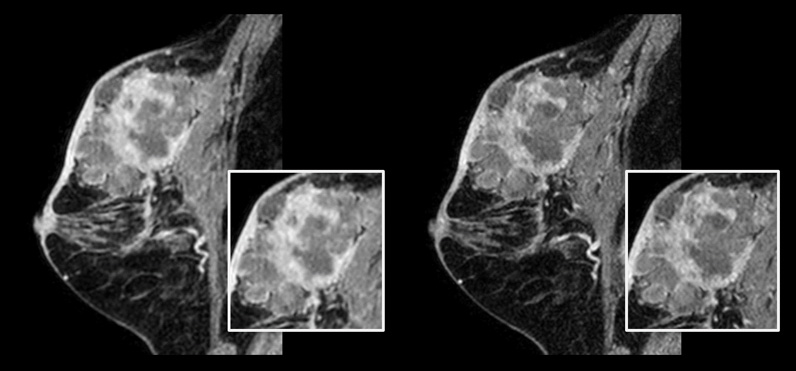

Patientin mit Brustkrebs

Links: Herkömmlicher 3D-mDIXON-XD-Scan mit isotroper Voxelgröße von 1,0 mm, Scandauer 2:22 Minuten Rechts: Compressed SENSE 3D-mDIXON-XD-Scan mit isotroper Voxelgröße von 0,8 mm, Scandauer 2:21 Minuten

Mit freundlicher Genehmigung von: Kurashiki Zentralkrankenhaus, Okayama. Japan

Bei Brustuntersuchungen ist eine hohe Auflösung wichtig, um sehr kleine Brustläsionen zu erkennen. Wir benötigen also T1- und T2-gewichtete 2D-Bilder in hoher räumlicher Auflösung, aber auch eine kurze Scandauer. Mit Compressed SENSE konnten wir die räumliche Auflösung und damit auch unsere Diagnosesicherheit erhöhen.“

Dr. Takashi Koyama, MD, PhD, diagnostischer Radiologe und Leiter des Radiologiezentrums und der diagnostischen Radiologie, Kurashiki Zentralkrankenhaus, Japan